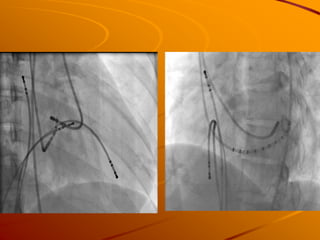

This 23-year-old woman presented with palpitations when carrying heavy materials and was found to have paroxysmal supraventricular tachycardia. She received adenosine and verapamil which terminated the arrhythmia. An electrophysiology study found atrioventricular reentrant tachycardia using an accessory pathway. Radiofrequency catheter ablation was performed and successfully eliminated conduction over the left posteroseptal and left lateral accessory pathways. She was diagnosed with manifest Wolff-Parkinson-White syndrome status post successful ablation.